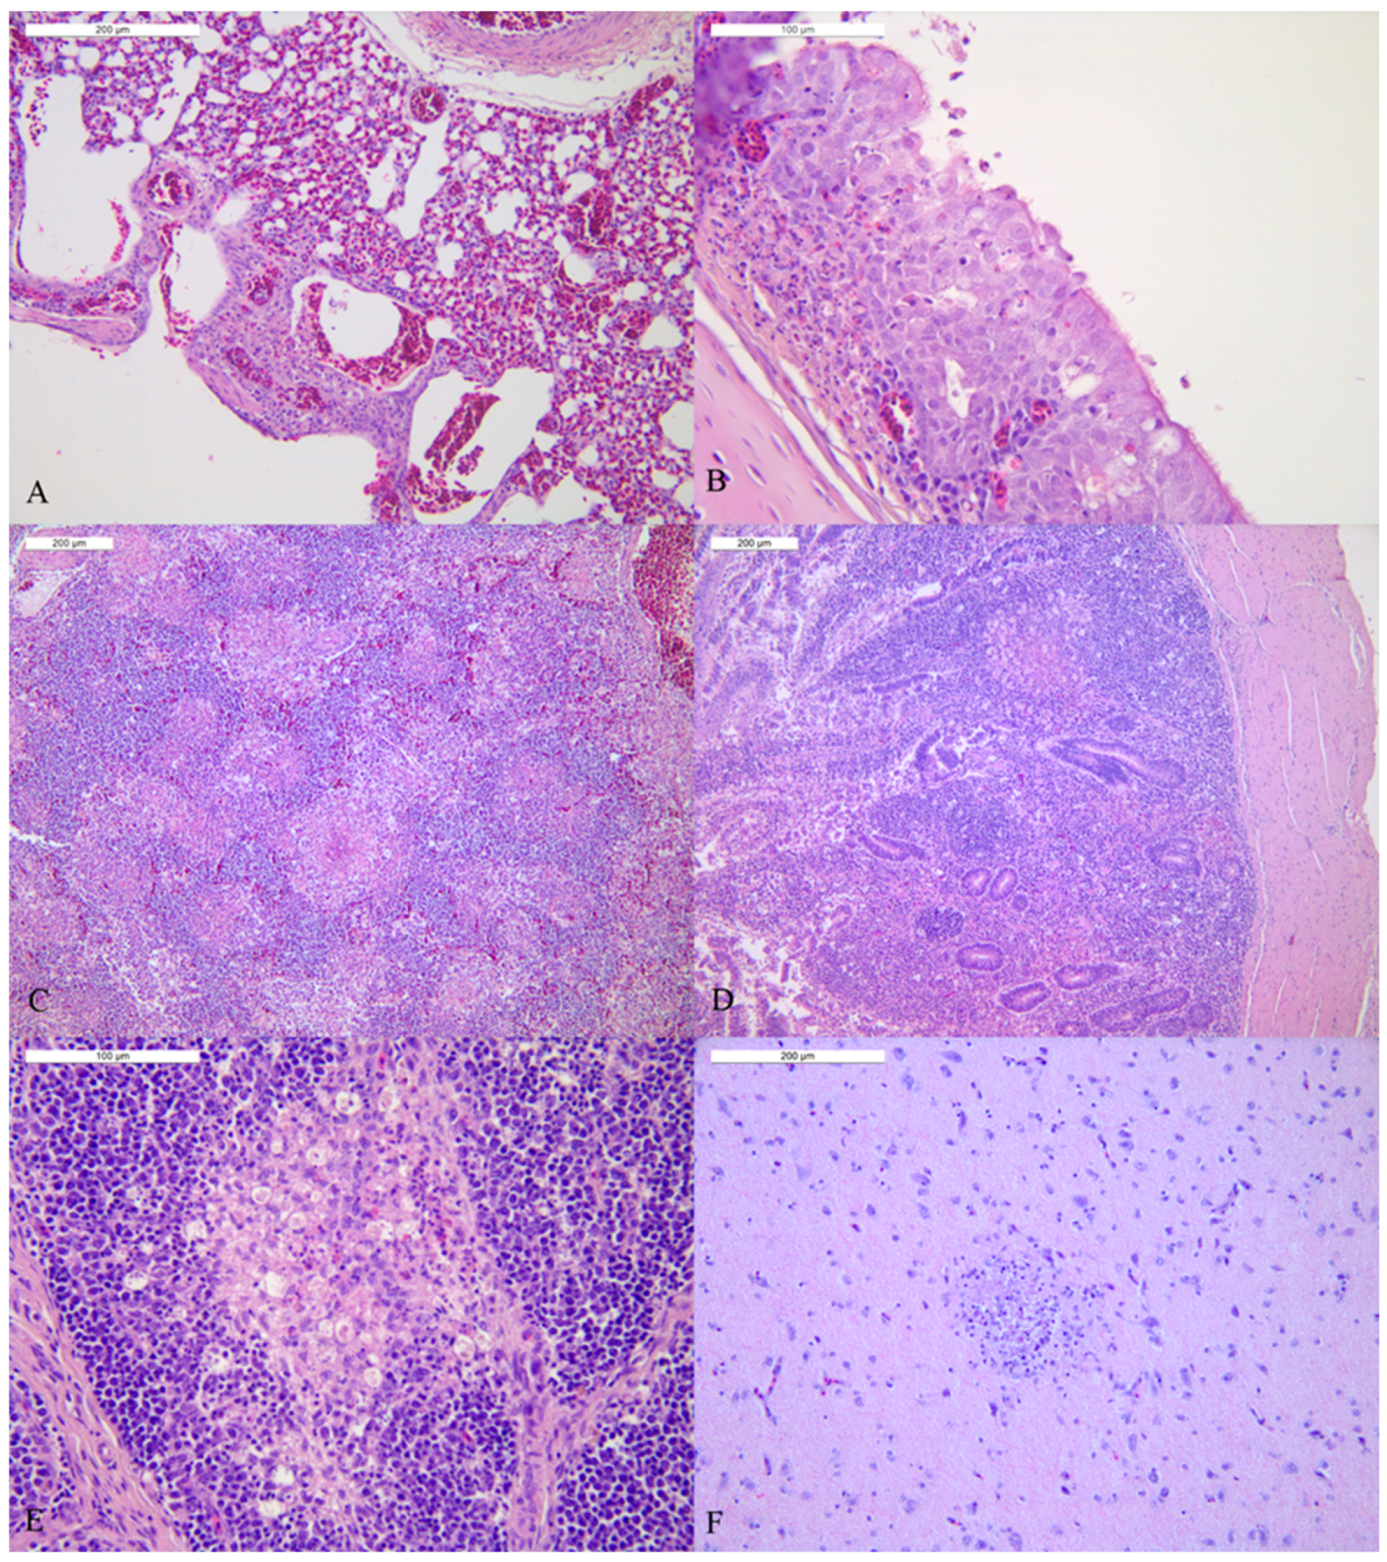

3.4. Study of Tissue Tropism and Pathogenesis (Pathobiology of HPAI Infection)

| House 3 | BRL1 | BRL2 | BRL3 | BRL4 | BRL5 | ||||||

| Organ | rRT-PCR (Ct) | IHC Score | rRT-PC (Ct) | IHC Score | rRT-PCR (Ct) | IHC Score | rRT-PCR (Ct) | IHC Score | rRT-PCR (Ct) | IHC Score | Predominant IHC Positive Cell Type/Tissue |

| Lung | neg | − | neg | n.d. | neg | n.d. | 25.03 | −/+ | 39.43 | − | Pneumocytes |

| Trachea | 37.68 | − | neg | n.d. | neg | n.d. | 23.83 | + | 38.46 | − | Epithelial cells, macrophages |

| Spleen | neg | n.d. | neg | n.d. | neg | n.d. | 23.86 | −/+ | neg | n.d. | Macrophages |

| Duodenum | neg | n.d. | neg | n.d. | neg | n.d. | 25.03 | −/+ | neg | − | Epithelium |

| Pancreas | neg | n.d. | neg | n.d. | neg | n.d. | 24.03 | −/+ | 38.31 | − | Acinar necrotic epithelium |

| Cecal tonsils | neg | n.d. | neg | n.d. | neg | n.a. | 24.05 | + | neg | n.d. | Debris in the crypts, epithelium, necrotic area, endothelium |

| Bursa of Fabricius | neg | n.d. | neg | n.d. | neg | n.a. | 22.25 | − | neg | n.a. | n.a. |

| Brain | neg | n.d. | neg | n.d. | neg | n.d. | 19.88 | + | neg | n.d. | Neurons, glial cells, ependymal |